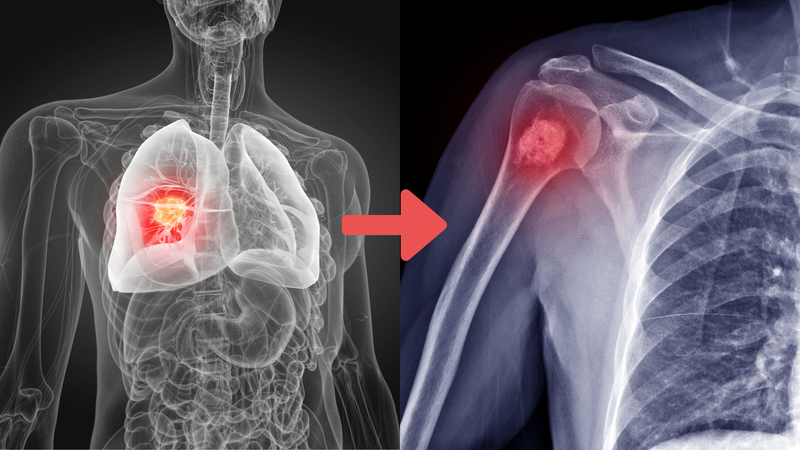

Di căn xương là một tình trạng nghiêm trọng xảy ra khi các tế bào ung thư từ một bộ phận khác của cơ thể lan sang xương. Nguyên nhân chính dẫn đến di căn xương thường là do các loại ung thư như ung thư vú, ung thư phổi, ung thư tiền liệt tuyến, ung thư thận và ung thư tuyến giáp. Các tế bào ung thư này có khả năng xâm nhập vào máu hoặc hệ bạch huyết, sau đó di chuyển và tạo ra các khối u mới trong xương.

Việc nhận biết sớm các triệu chứng của di căn xương là rất quan trọng để kịp thời điều trị và kiểm soát bệnh. Nếu bạn hoặc người thân có các triệu chứng trên, hãy liên hệ với bác sĩ ngay để được tư vấn và tiến hành các xét nghiệm cần thiết như X-quang, MRI hoặc PET scan. Điều trị di căn xương thường bao gồm sử dụng các loại thuốc điều trị di căn xương và có thể kết hợp với các phương pháp tiên tiến khác tùy thuộc vào tình trạng cụ thể của bệnh nhân.